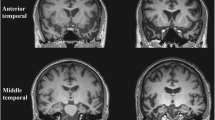

The clinical syndrome of SD is associated with a characteristic neuroanatomical profile, which usually secures the diagnosis (see Fig. 1). Structural volumetric MRI typically reveals selective atrophy of the antero-inferior temporal lobe, usually bilateral but asymmetric, and frequently more severe in the left hemisphere. Atrophy is most marked in temporal polar cortex, fusiform gyrus and mesial temporal structures (Chan et al. 2001) with a clear antero-posterior gradient; knife-blade atrophy at the pole gives way to relatively normal cortex in more posterior temporal and peri-Sylvian regions. This atrophy profile distinguishes SD from both frontotemporal dementia (Rosen et al. 2002) and Alzheimer’s disease (Chan et al. 2001). As might be anticipated in an essentially sporadic disease, little information is available concerning the very earliest anatomical changes in SD; however, longitudinal imaging using MRI volumetry (Czarnecki et al. 2008; Rohrer et al. 2009) and tensor-based morphometry (Brambati et al. 2009) has shown that disease evolution is associated with extension of atrophy to inferior frontal, insular and more posterior temporal lobe cortices and to the contralateral temporal lobe, so that the less affected temporal lobe ‘catches up’ over the course of the disease; post mortem data indicate a largely symmetric distribution of atrophy (Davies et al. 2009). This evidence further strengthens the case for regarding the left and right temporal lobe ‘variants’ of SD as a single coherent clinic–anatomical syndrome (Seeley et al. 2005). Atrophy rates during the phase of early established clinical disease are sufficiently large and uniform that either whole brain or regional lobar atrophy could feasibly serve as a biomarker in future clinical trials: in terms of projected sample sizes required to detect a moderate MRI treatment effect, SD compares favourably with other FTLD subtypes (Rohrer et al. 2009; Knopman et al. 2009; Krueger et al. 2010; Gordon et al. 2010).

Representative coronal T1-weighted MRI sections of the brain of a patient with semantic dementia (clinical disease duration 3 years). The sections show key structures at the level of the temporal pole (TP), anterior temporal lobe (aTL) and posterior temporal lobe (pTL); the left hemisphere is shown on the left in all sections. The sections show a characteristic profile of asymmetric focal atrophy most markedly affecting the anterior and inferior temporal lobes